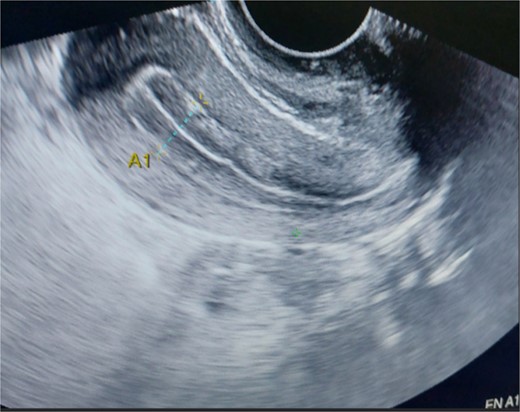

A 26-year-old nulliparous lady from a rural area was referred to emergency from a primary health care centre with a failed attempt to remove an impacted uterine foreign body. On per speculum examination, an impacted hard pipe-like structure was protruding from the cervix. The patient gave a history of foreign body insertion 9 years back, however, failed to provide a detailed account of the mode of insertion or history of sexual assault. She went to seek medical care only after developing profuse foul-smelling discharge and chronic pelvic pain. Removal was attempted under local anaesthesia but failed. Transvaginal scan showed a bulky uterus with an apparently normal endometrial thickness and echotexture; however, the cervical canal was distended with an echogenic area and areas of calcification (Figs 1 and 2). She was taken up for removal of the foreign body under general anaesthesia. As a hard pipe-like structure was already protruding, removal was tried by grasping it with a Kocher’s forceps. After multiple attempts part of the foreign body was removed. Hysteroscopy showed that the lower endocervical canal was clear and a ring-like structure occupied the upper endocervical canal. Removal under direct vision using a hysteroscopic grasper was attempted but failed due to the impaction and size of the object and the hysteroscope could not be negotiated beyond the object. A laparotomy was performed and after an assessment of anatomy and tactile sensation to assess accessibility, incision on the posterior surface of the uterus was given (Figs 3 and 4) and the object was removed (Fig. 5). The incision was closed in two layers. Intercede was placed at the repair site. An extended course of antibiotics was given for 7 days. Post-operative recovery was uneventful. Contraception for at least 1 year, the need for proper antenatal care, the risk of rupture, and mandatory caesarean delivery were counselled to the couple.